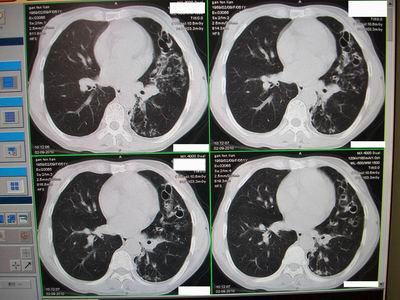

标题: CT24546:支气管扩张?多发性肺囊肿?请高手发表意见吧 [打印本页]

标题: CT24546:支气管扩张?多发性肺囊肿?请高手发表意见吧

临床:女性,51岁,一年来咳嗽、咳痰,反复发作,近两个月带少许血丝。

查体:精神较差,消瘦,余未见明显异常。

图片如下:\

“印戒征”,支扩伴感染

病变主要延肺动脉走形,多发囊状影较小且壁厚,还得先考虑---支扩伴感染。

支扩:腔小、壁厚、多液平;多发性肺囊肿:腔大、壁薄、少液平,本例符合支扩合并感染